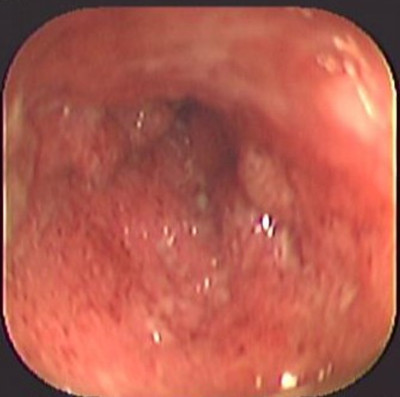

Colitis ulcerosa crónica inespecífica

Envíado por Dr. Carlos Ernesto Arévalo